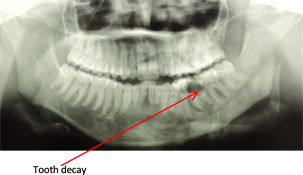

Figure 2. Tooth Caries.

Tooth decay (Figure 3) and dental avulsions were the largest causes of maxillary osteitis in our study with 79.41% of the cases. In many cases, tooth decay will cause cellulitis that will not be treated or will be poorly managed.

Tooth decay and dental avulsions were the most commonly identified etiologies in our study with 79.41% of the cases, followed by periodontal diseases (13.23% of cases). The distribution of osteitis cases based on etiologies is illustrated in the following table of surgical reports (Table 1).